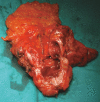

Intermittent gastric outlet obstruction due to a gallstone migrated through a cholecysto-gastric fistula: a new variant of "Bouveret's syndrome"

Bouveret's syndrome, defined as gastric outlet obstruction due to a large gallstone, is still one of the most dramatic biliary gallstone complications. Although new radiological and endoscopic techniques have made pre-surgical diagnosis possible in most cases and the death rate has dropped dramatically, "one-stage surgery" (biliary surgery carried out at the same time as the removal of the gut obstruction) should be still considered as the gold standard for the treatment of gallstone ileus.In this case, partial gastric outlet obstruction resulted in an atypical and insidious clinical presentation that allowed us to perform the conventional one-stage laparatomic procedure that completely solved the problem, thus avoiding any further complications.